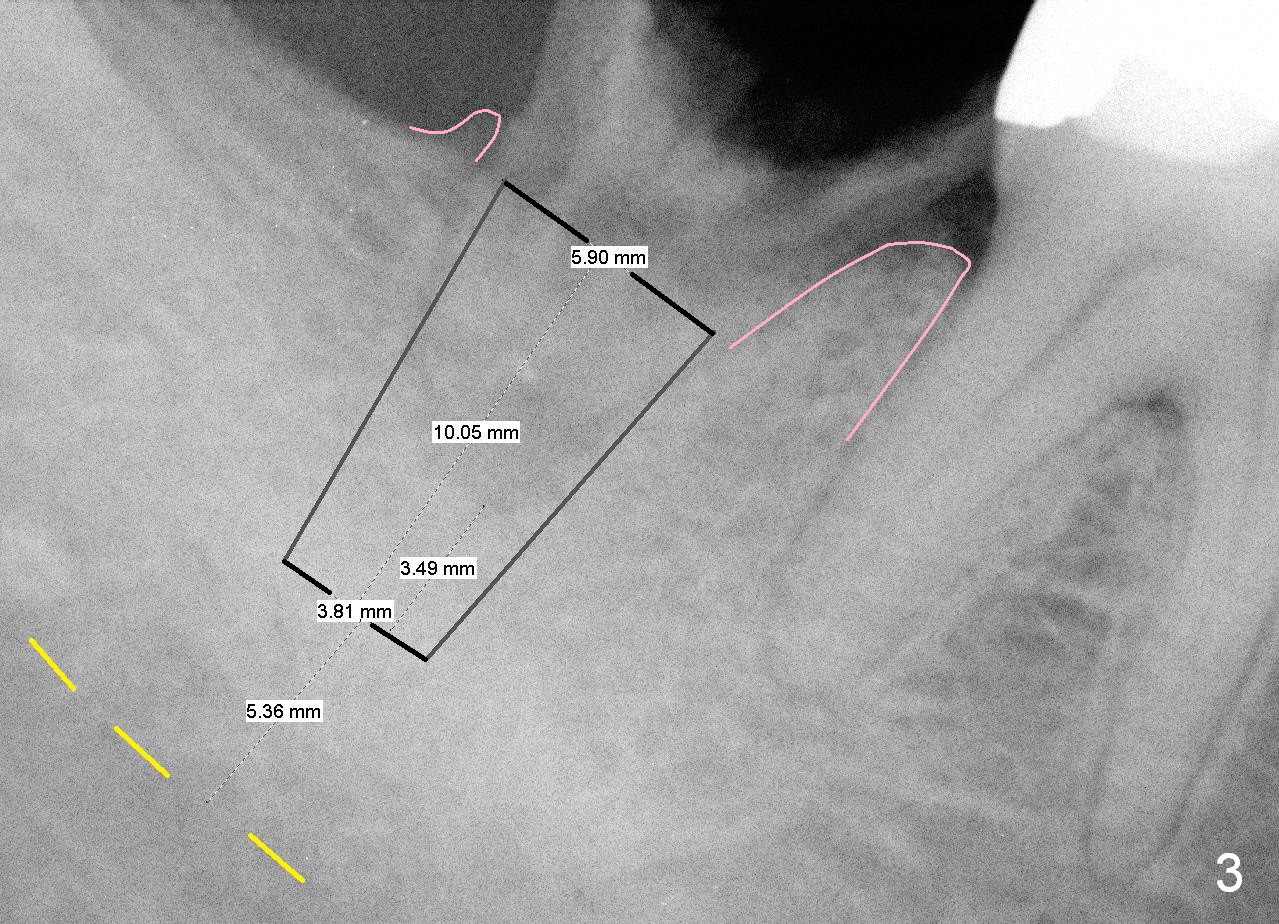

A 35-year-old man wants to restore the tooth #31. The root is conical in shape (Fig.1). It is natural to start osteotomy at the apex of the socket and along the long axis of the socket (Fig.2 red arrow), but the end result is that the immediate implant (Fig.3 black area) is not aligned well with the mesial and distal crests (pink areas; yellow dashed line: upper border of the Inferior Alveolar Canal). If this bone-level implant is level with the mesial crest, the distal threads will not be covered by the native bone. The distal threads may be exposed.